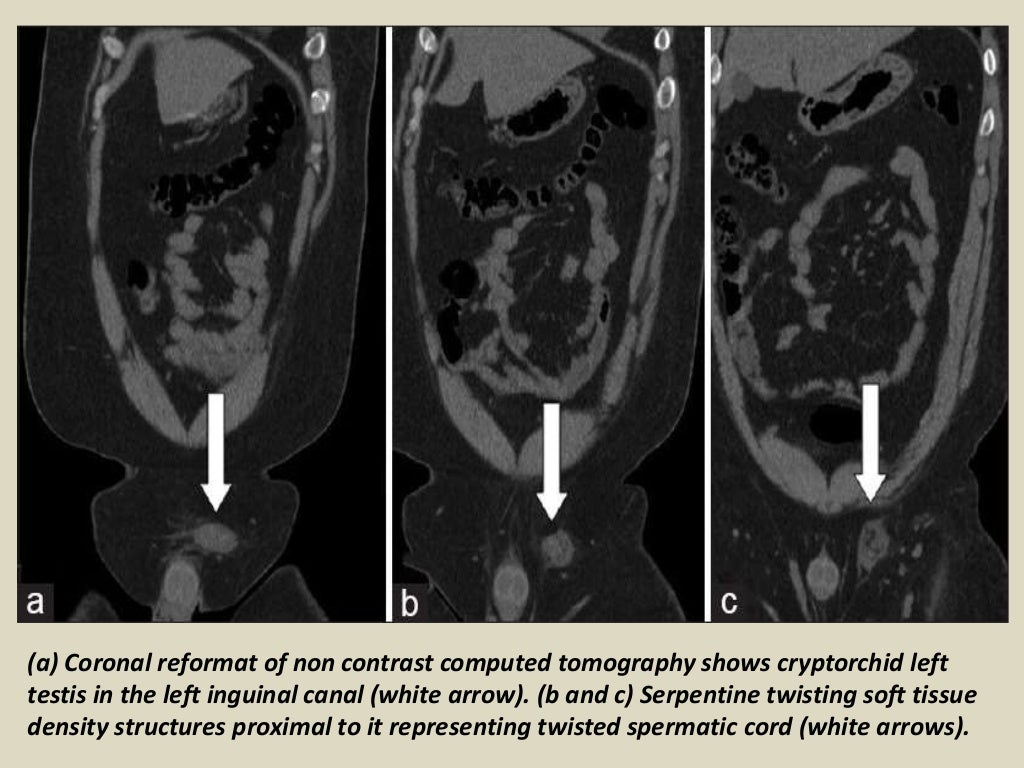

Presentation1, radiological imaging of undescended testis. What Is Undescended Testes In Tagalog These are the testes and. Male reproductive system diseases account for 14% of the burden of health in filipino men. And 10% of the time, it’s bilateral or affecting both testes. Instead, it’s in the groin or lower abdomen. Undescended testes is when one or both of the male testes have not passed down (descended) into the scrotal sac. Cryptorchidism. What Is Undescended Testes In Tagalog.